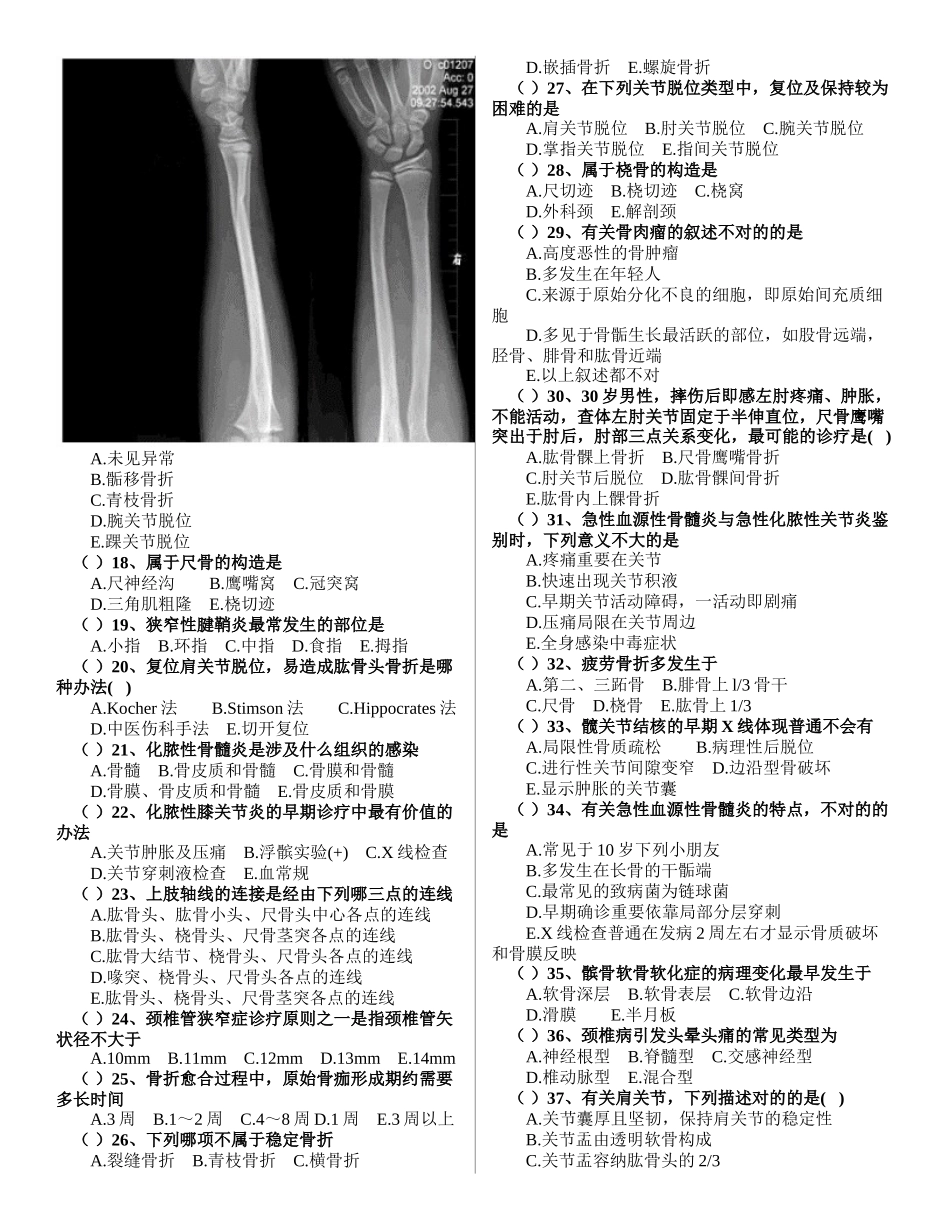

出科考试题(骨科)姓名 成绩一、A1/A2 型题(100 分) ( )1、缺血性骨坏死最易发生在下列哪种骨折 A.月骨骨折 B.手舟骨骨折 C.大多角骨骨折 D.头状骨骨折 E.尺骨茎突骨折 ( )2、骨软骨瘤切除范畴是 A.骨段切除 B.纤维膜,软骨帽 C.切除肿瘤,搔刮邻近髓腔 D.纤维膜、软骨帽、病骨 E.纤维膜、软骨帽、病骨,基底周边部分正常骨和骨膜 ( )3、骨网织细胞肉瘤属于 A.骨组织肿瘤 B.软骨组织肿瘤 C.纤维组织肿瘤 D.骨髓组织肿瘤 E.滑膜组织肿瘤 ( )4、下列哪种状况可排除骨折的可能性 A.受伤部无畸形 B.无骨摩擦音 C.无反常活动 D.局部肿胀与淤斑 E.以上均不能排除 ( )5、显微血管端-端吻合时,为确保血管畅通,减少血栓形成,常采用下列哪种办法 A.端对端间断缝合 B.管壁轻度内翻,血管内膜达成良好的对合 C.管壁轻度外翻,血管内膜达成良好对合 D.血管内膜轻度外翻缝合,再将血管外膜覆盖加强,避免漏血或喷射状出血 E.管壁全层外翻缝合 ( )6、男性,6 岁。X 线检查诊疗锁骨青枝骨折。对的的解决是 A.三角巾悬吊患肢 3 周 B.手法复位,“8“字绷带外固定 C.手术内固定 D.不予解决 E.卧床 2 周 ( )7、原发性恶性骨肿瘤的普通 X 线体现是 A.骨质缺损,边沿清晰,骨膜反映明显 B.骨质破坏,边界不清,骨膜反映不明显 C.骨质密度增高,境界不清,骨膜反映明显 D.骨质破坏,边沿不清,骨膜反映明显 E.骨质缺损,边沿清晰,骨膜无反映 ( )8、成人股骨头的血液不来源于 A.股骨头圆韧带内的小凹动脉 B.股骨干滋养动脉升支 C.旋股内侧动脉分支 D.旋股外侧动脉分支 E.臀上动脉分支 ( )9、有关骨肿瘤,下列哪项是错误的 A.脊索瘤来源于脊索组织,好发于上颈椎及骶椎,好发病于 40 岁以上,发展缓慢,属良性肿瘤 B.骨网状细胞瘤来源于髓网状细胞,多见于青壮年,好发于长管状骨 C.骨纤维肉瘤,成年、老年均可发病,疼痛轻,转移较晚,预后较好 D.滑膜肉瘤来源于关节滑膜、腱鞘及滑囊,多见于 20~40 岁 E.骨巨细胞瘤好发于膝关节两端的骨端及桡骨远端 ( )10、下面哪项不是股骨颈骨折的典型畸形体现 A.大转子上移征 B.伤侧足呈 45°~60°外旋畸形 C.患肢缩短 D.伤侧足呈 90°外旋畸形 E.股骨大转子顶端在 Nelaton 线之上 ( )11、有关胸锁关节,下列描述对的的是( ) A.属于单轴关节 B.由锁骨的胸骨端和胸骨的锁切迹构成 C.关节内无关节盘 ...